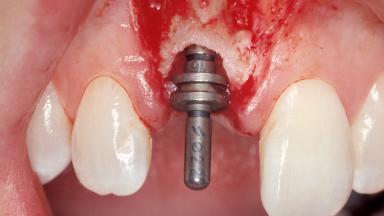

Immediate Placement of an Implant in a Maxillary Right Central Incisor Site

A 30-year-old female patient was referred to the office for the treatment of tooth 11. Her chief concern at the initial visit was to inquire, “Why is my tooth pink?” Upon clinical examination, it was determined that tooth 11 had a previous history of trauma and that the clinical crown had become noticeably pink in color as a result of internal resorption. This diagnosis was confirmed radiographically, indicating a large radiolucency involving the central and distal portions of the clinical crown. It was determined that restoration of this tooth was not possible, and that extraction was indicated. The presence of a mid-line diastema, which the patient wanted to reproduce, directed the treatment plan for tooth replacement utilizing a dental implant.

| Placement Protocol | Immediate implant placement |

| Tooth Site | Maxillary incisor or canine |

| Socket Morphology | Single-root socket |

| Socket Integrity | Sufficient, with intact bone walls |

| Bone Volume | Sufficient, with intact walls |